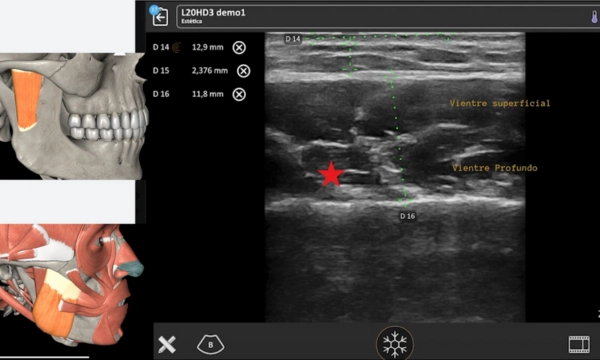

- Anatomía aplicada a bonta

- Bruxismo

- Síndrome miofascial